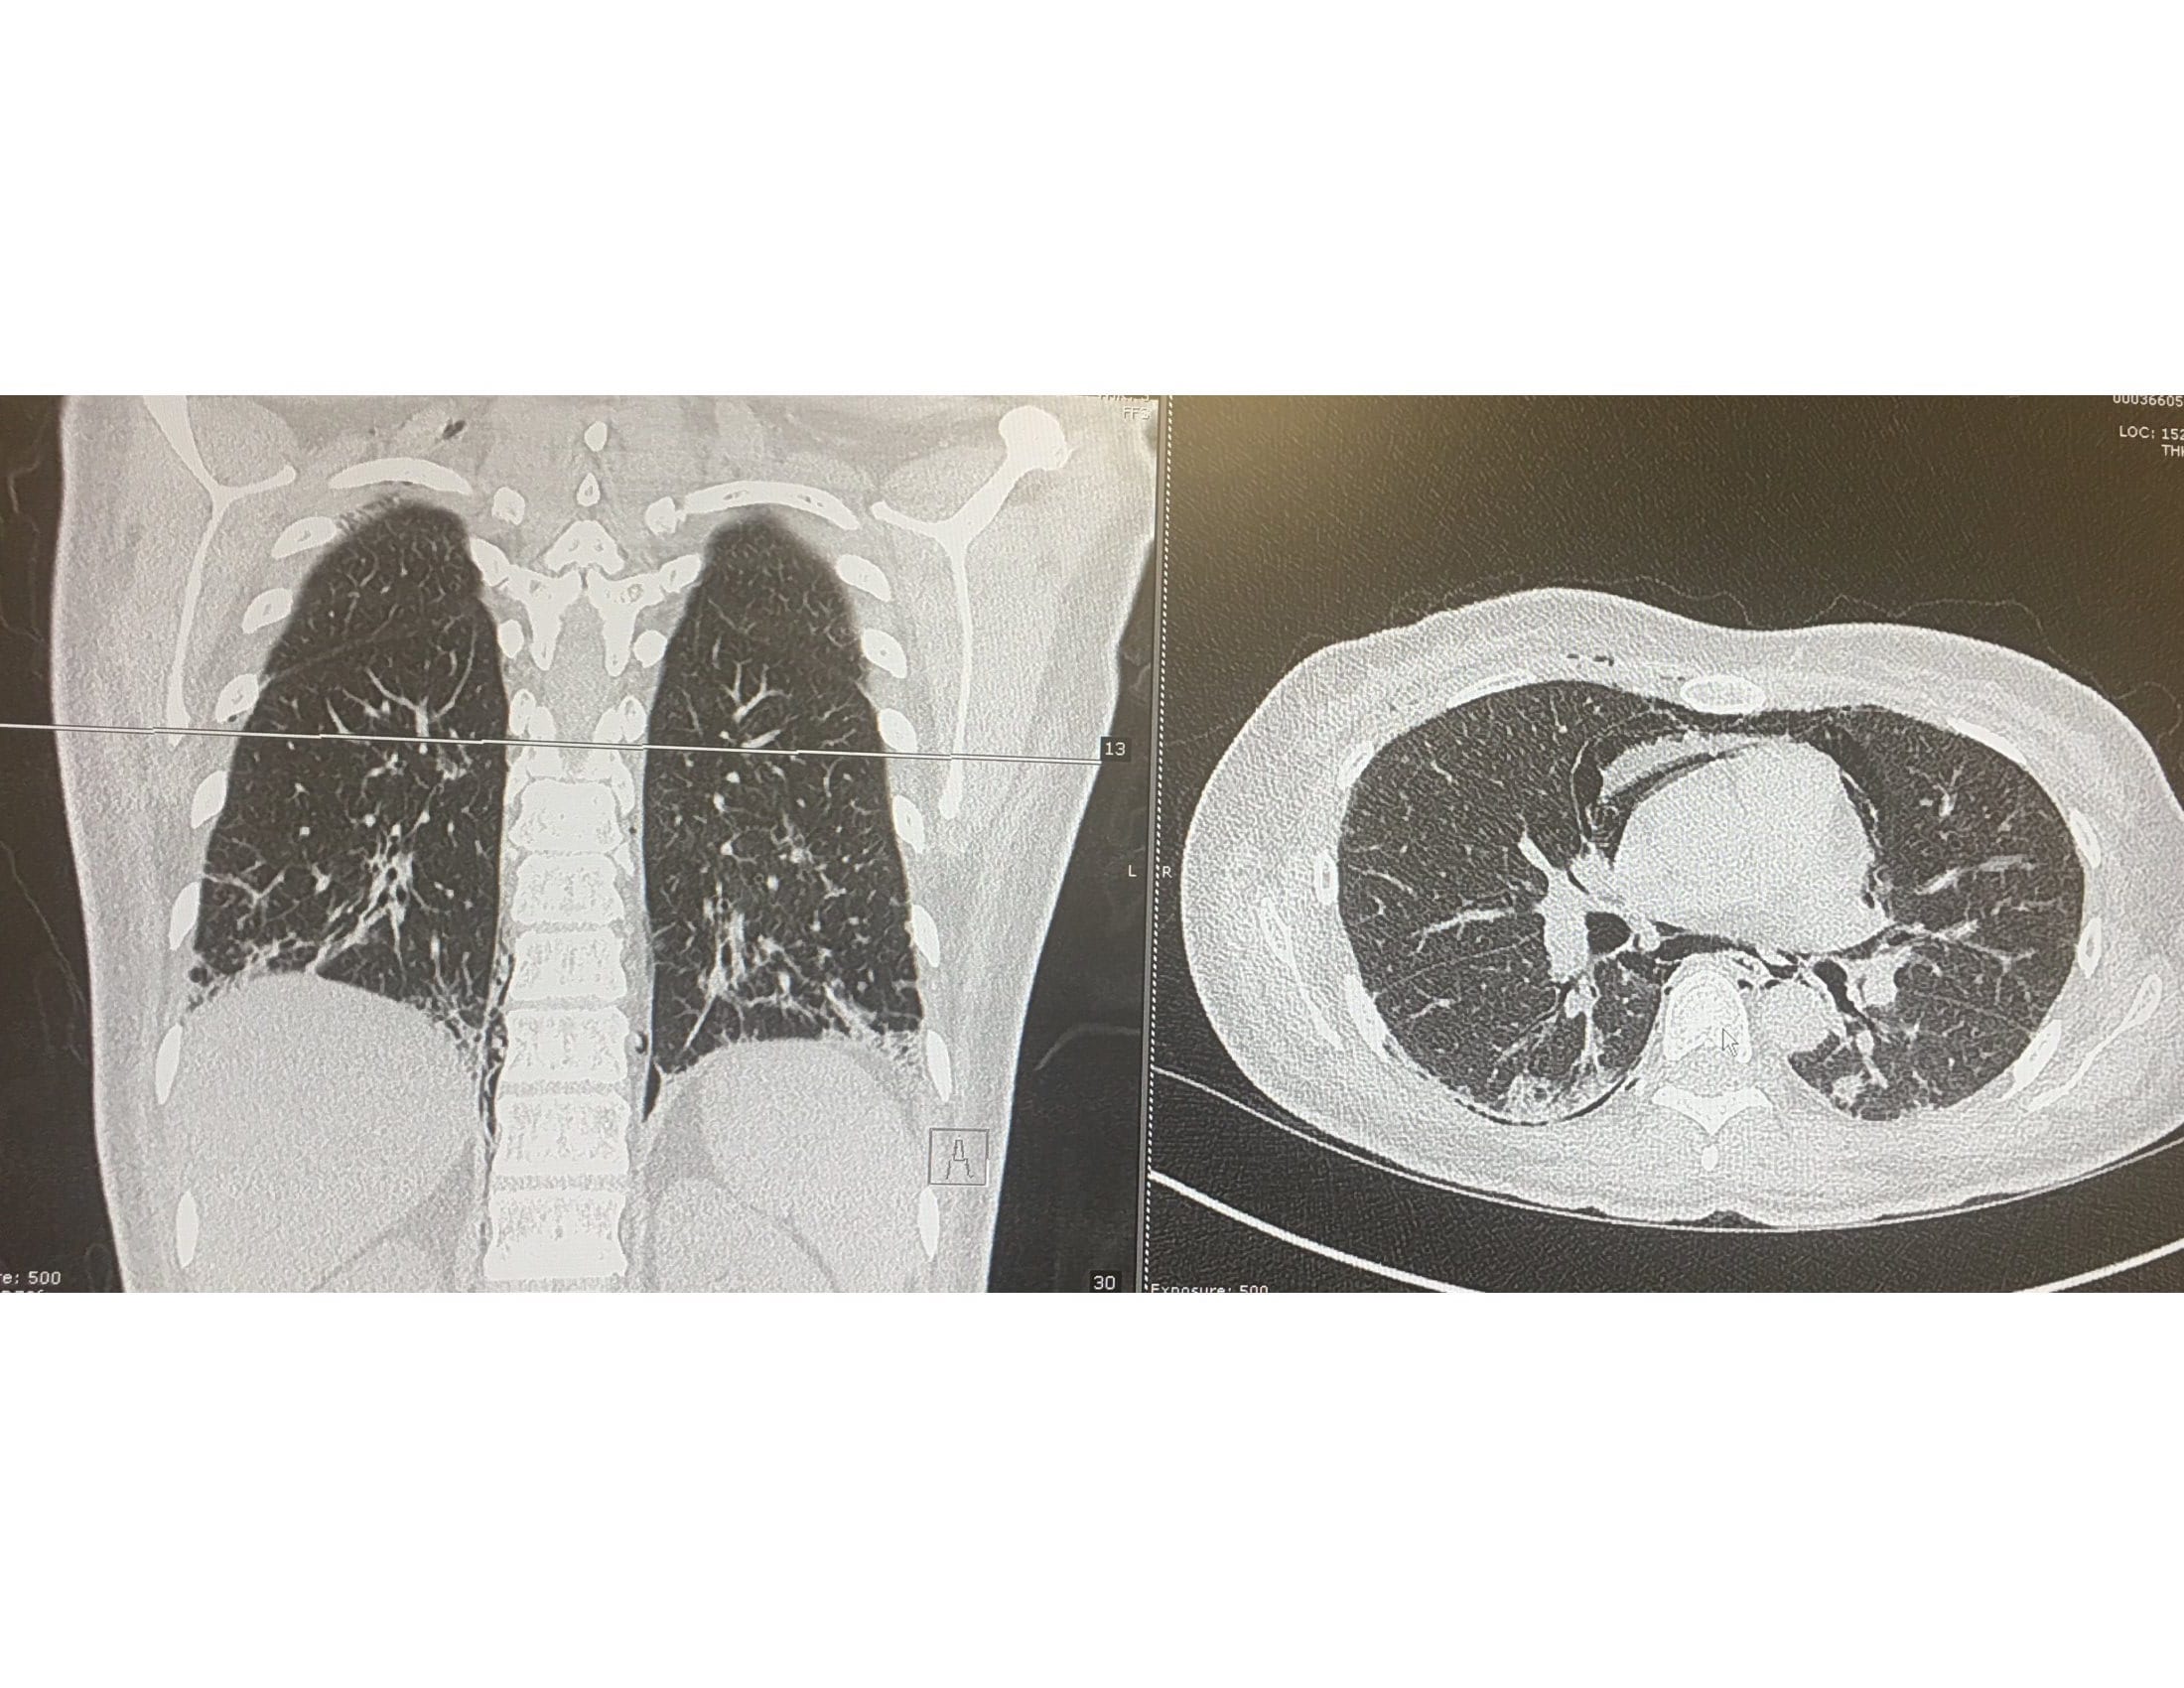

Case Presentation: A 33-year old female presented with 24 hours of subjective fever, severe neck, and chest pain. She was seen 6 months ago for arthralgia of the metacarpophalangeal, proximal interphalangeal and knee joints. Her home medication included Prednisone and Hydroxychloroquine prescribed for Lupus. Her physical examination demonstrated neck crepitus, bilateral crackles, ulcers in the tip of the fingers, erythroderma in elbows, knuckles and eyelids. CT chest revealed pneumomediastinum and right chest wall soft tissue emphysema. There were bilateral pneumothoraces and ground-glass opacities involving lower lobes bilaterally and bibasilar interlobar septal thickening. Laboratory data were significant for normal CPK levels. Anti-Jo1, PL-7, PL-12, Mi2, dsDNA antibodies were negative. ANA ab and Anti mitochondrial M2 were positive. O2 supplementation, Prednisone, Rituximab, and Mycophenolate were given since admission with marked improvement of the symptoms. Upon discharge, she was seen by her rheumatologist who diagnosed Antisynthetase syndrome after new laboratories were ordered.

Discussion: Antisynthetase syndrome is a very uncommon disease, with a reported annual incidence of two new cases per one million adults. This is probably an underestimation caused by a lack of familiarity with this syndrome which criteria were described less than ten years ago. Connor’s criteria include the presence of antibodies against aminoacyl t-RNA synthetase along with features of interstitial lung disease, myositis, Raynaud’s phenomenon, and arthritis. Anti-histidyl antibody (Jo-1) is the most commonly detected antibody (30%).Clinical features of this patient including interstitial lung disease, Goitron papules, mechanical hands, and polyarthritis suggested Antisynthetase syndrome. Imaging studies supported the diagnosis because common findings reported in the literature include ground-glass opacities and interlobar septal thickening as seen in this patient. However, this is a challenging scenario because the patient did not meet diagnostic criteria due to a lack of specific antibodies. This could be explained by autoantibody levels fluctuation depending on disease activity. Also, only a few aminoacyl transfer RNA synthetase antibodies have been identified, many are still not available for laboratory detection.In terms of treatment, there are not clinical trials due to the rarity of this condition. However, cases reported indicating that high dose steroids are the most effective medication in controlling acute pulmonary disease associated with this syndrome. They are used in combination with mycophenolate, and rituximab to improve the prognosis. Complications like spontaneous pneumothorax are managed with oxygen and supportive therapy on stable patients.